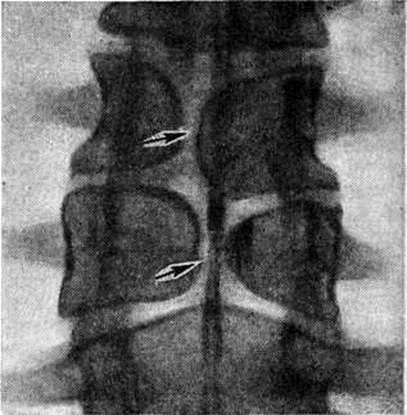

Локализация расщелины в теле или дуге позвонка может быть самой различной (рисунок 2). Рентгенологически легче распознаются расщелины, ориентированные в сагиттальной плоскости, которые лучше видны на рентгенограмме в прямой проекции. Расщелины в боковых отделах дуг и тел видны на рентгенограммах в боковой проекции, а иногда только на томограммах. При локализации в телах позвонков (spina bifida anterior) щель делит тело позвонка на две части, каждая из которых имеет на рентгенограмме в прямой проекции клиновидную форму. Чаще обе части тела позвонка расположены симметрично, напоминают по виду крылья бабочки — так называемый бабочковидный позвонок. Однако клиновидные части тела позвонка могут быть и асимметричными (рисунок 3). В процессе роста тела соседних позвонков приспосабливаются к форме аномальных позвонков.

Чаще встречаются дефекты в дугах позвонков, особенно нижних поясничных и крестцовых. Наиболее типично незаращение дуги по средней линии с расщеплением и недоразвитием, а иногда и отсутствием остистого отростка. Эта локализация Спина бифида легко выявляется на рентгенограмме в прямой проекции (рисунок 4). Реже расщелина локализуется в дуге между суставными отростками с одной или с обеих сторон — спондилолиз (рисунок 5). Диагностика Спина бифида этой локализации сложна, если она не сочетается со спондилолистезом (смотри полный свод знаний). При подозрении на спондилолиз обязательна рентгенография в двух проекциях, а при недостаточной информативности рентгенограмм необходимо томографическое исследование в боковой проекции (смотри полный свод знаний: Томография).